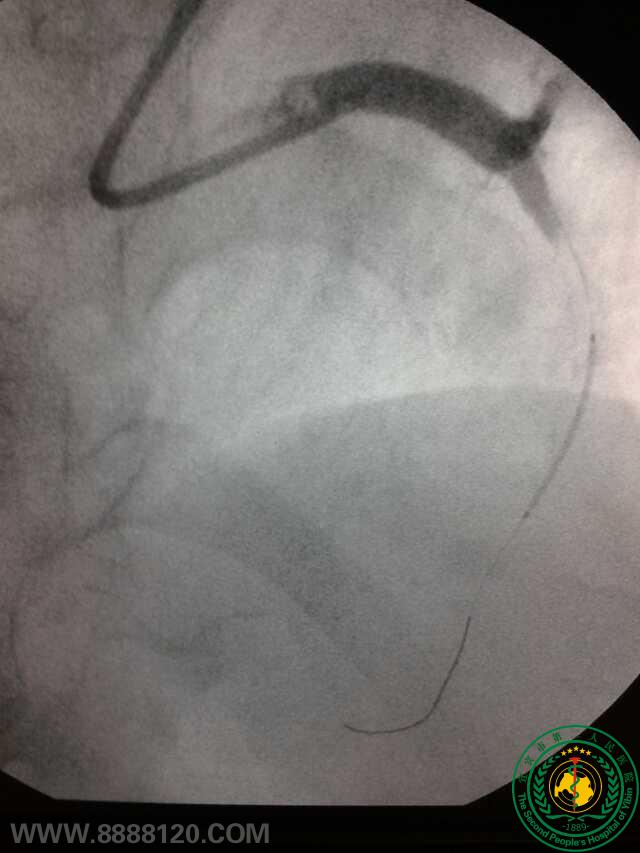

冠脉治疗新技术——宜宾首例冠脉旋磨术

冠脉治疗新技术——宜宾首例冠脉旋磨术6777